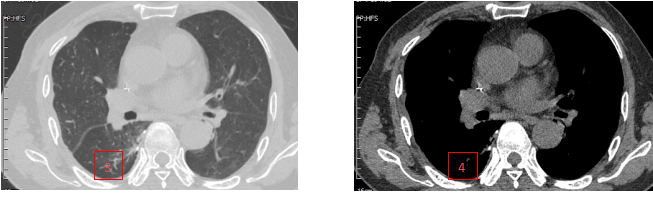

术 前

术后2月

1、胸腔积液(肺窗);2、胸腔积液(纵隔窗);3、1、胸腔积液(肺窗);2、胸腔积液(纵隔窗);3、胸腔积液消失(肺窗);4、胸腔积液消失(纵隔窗)。